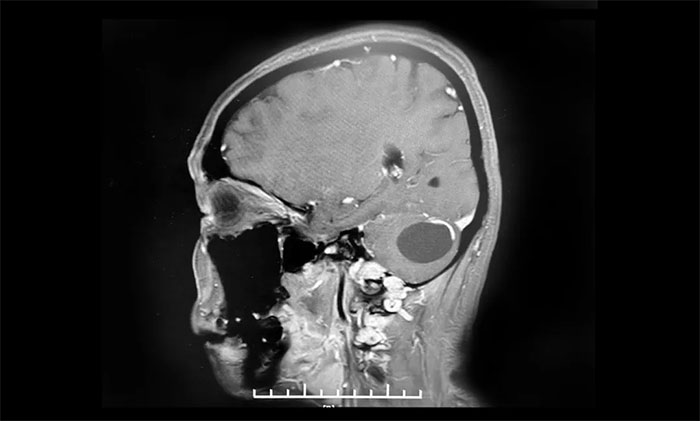

6個月前,小妍在無任何誘因的情況下出現(xiàn)了頭暈,一旦發(fā)作就覺得天旋地轉(zhuǎn),2月前在頭暈發(fā)作時還會出現(xiàn)枕部頭疼,10余天前又出現(xiàn)了行走時步態(tài)不穩(wěn)癥狀。小妍的母親趕緊將小妍帶到了當?shù)蒯t(yī)院檢查,經(jīng)行頭顱MRI顯示,在小妍的左側(cè)小腦半球有一長T1長T2圓形囊實混合占位,大小約4.2*3.2cm,考慮為“腦血管母細胞瘤”,并且合并腦積水,建議其手術(shù)治療。

▲ 右側(cè)小腦血管母細胞瘤,大小約34x34mm